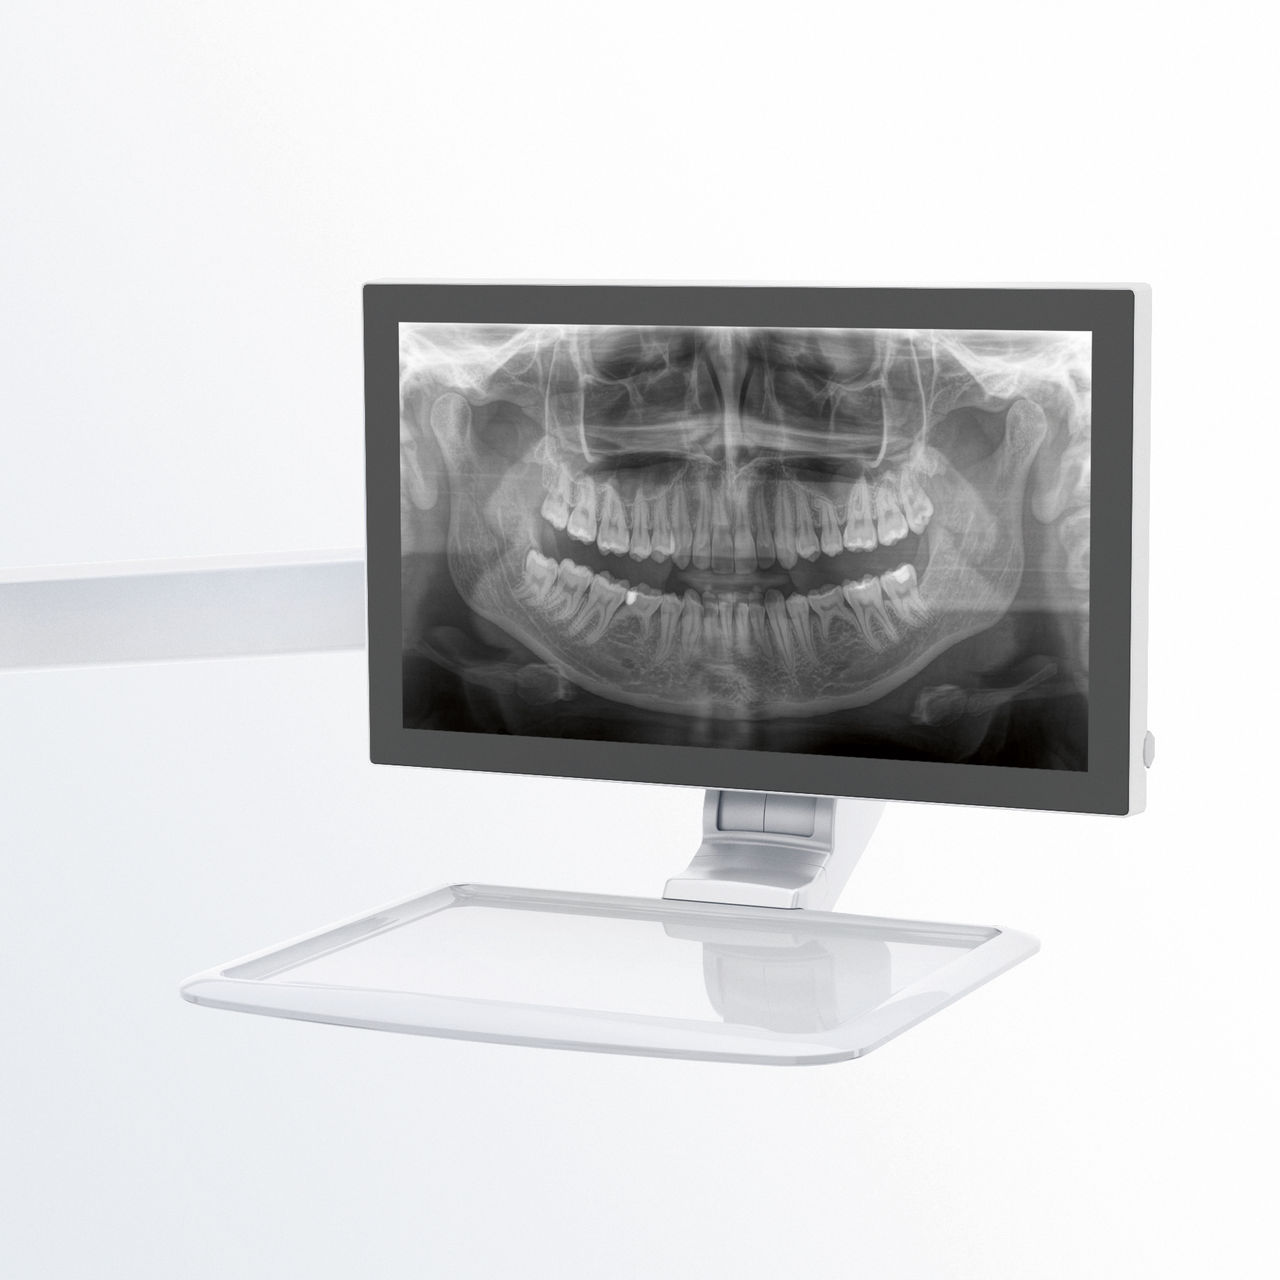

Bilder der Arbeit mit unserem Patientenpositionierungs- und Bildassistenten-Konzept

Intuitive Einstellungen über das EasyPad